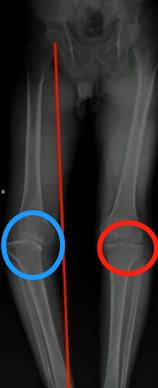

看上图这个病人,左膝是痛风性关节炎的患侧,右膝相对正常。左右膝对比就可以看出,左膝因为痛风性关节炎的影响,关节力线已经不好,即髋膝踝3点的连线不通过,膝关节,出现严重内翻膝的情况。而且关节间隙(圆圈处)已经不平衡,导致软骨磨损严重。且患者出现部分骨缺损情况,就是这个骨头没有了,无法承重了。

此时只能行全膝关节置换手术,并配合骨重建,重新换一个完整好用的人工关节。自体本身的关节,已经像一个千疮百孔的废胎,不能使用了。